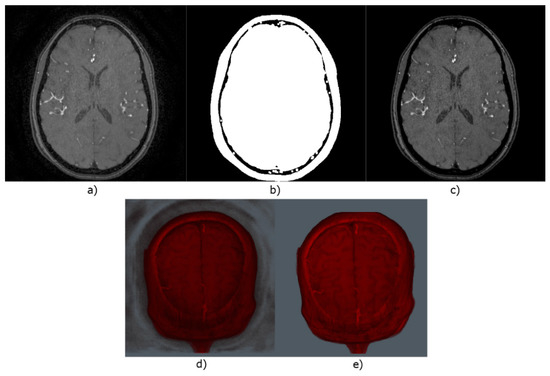

- Image preprocessing